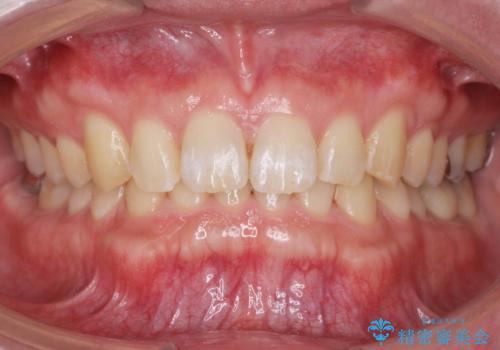

ディープバイトのマウスピース矯正

担当医 大元洋佑

ディープバイト改善のためのインビザライン治療

担当医 河口智英